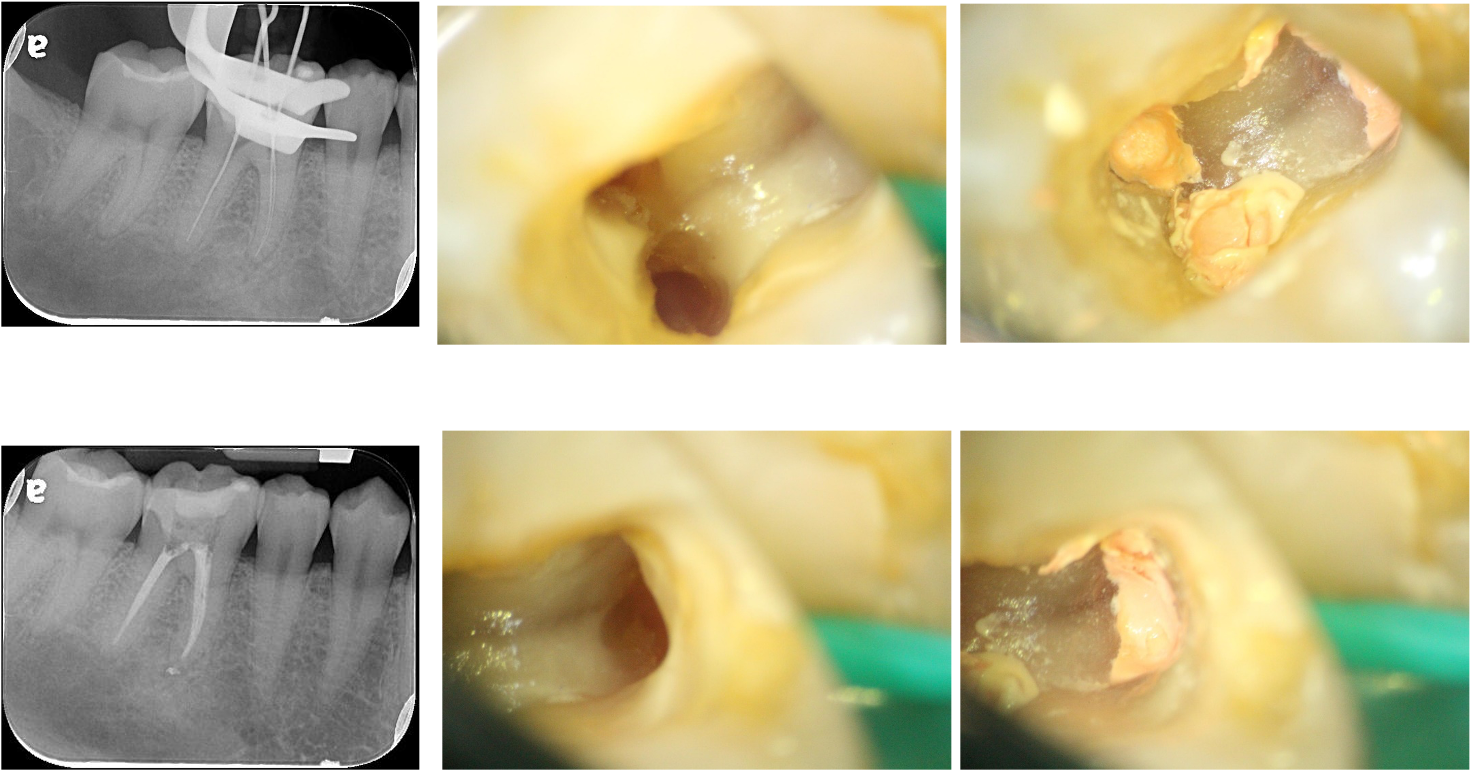

先進行非手術顯微根管治療

牙齒拔出,刮除根尖病變